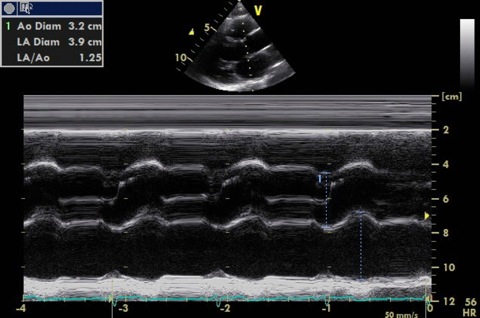

M-mode

Through tips of aortic valve leaflets

- Assess valve opening

- Measure aorta (end diastole) and LA (end systole)